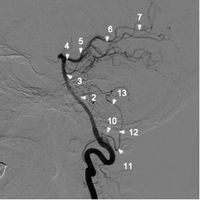

椎動脈側點陣圖1

椎動脈造影21 小腦後下動脈瘤 2a 小腦前下動脈和小腦後下動脈共乾(2b小腦前下動脈)

3 小腦上動脈 4 大腦後動脈P1段

5 大腦後動脈P2段 6 大腦後動脈P3段

7 大腦後動脈P4段 8 椎動脈

9 基底動脈 10 小腦後下動脈延髓前段

11 小腦後下動脈延髓外側段 12 小腦後下動脈延髓後段

13 小腦後下動脈扁桃體上段正常血管造影解剖

小腦後下動脈是椎動脈入顱後發出的最重要的分支,在側位上顯示最清楚,分為4段2個袢。第1段也稱延髓前段,在延髓池內走行並從橄欖體下方繞過;第2段也稱延髓外段,在小腦延髓裂內走行,並形成尾側袢;第3段也稱延髓後段,為小腦後下動脈達到延髓後緣並在後髓帆後的上升部;第4段也稱扁桃體上段,為小腦後下動脈在扁桃體上方行走時形成的第二袢即頭側袢。小腦前下動脈和小腦後下動脈共乾是一種較常見的變異,有時一乾同時供應雙側小腦後下動脈也屬正常變異,個別情況下,椎動脈的終支延續為小腦後下動脈,此時後循環的血供主要依靠對側椎動脈。

小腦前下動脈在正位和Towne位上很易識別,起自基底動脈近端並橫行向外走行進入橋腦小腦角池,在內耳門附近形成一向外的袢捲曲進入內聽道。側位上有一特徵性單弧或雙弧彎曲,呈N形或M形。

小腦上動脈近端在正位上顯示良好,但遠端在側位上顯示清晰。小腦上動脈的起始段與大腦後動脈平行走行,二者相距僅數毫米。